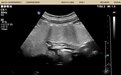

如今,青岛市中心医院腹部超声科已成熟开展胃、十二指肠检查新技术——胃超声造影检查,让患者能够轻松了解自身胃的健康状况,早日发现胃部疾病。这项检查无痛、无创、无副作用,安全性好、舒适度高、诊断准确率高,两年多来已经为近2000例患者完成筛查诊断,积累了丰富的临床经验。

胃超声检查是指患者空腹服用造影剂后进行的胃、十二指肠B超检查。超声原理为造影剂迅速消除胃肠内气体、黏液的伪像干扰,在胃、肠腔形成一种均匀分布的较强回声界面,造影剂均匀黏附于黏膜表面,清晰显示胃、十二指肠壁结构,为腹腔结构提供了一个声窗,还可以帮助观察以往难以发现的邻近脏器病变。

胃超声无创、无痛、方便快捷,无需麻醉插管、无副作用、无辐射,可以实时动态观察胃部情况,如胃排空、反流、蠕动等;不仅观察胃黏膜病变,而且可以发现来源于胃壁的病灶,并且定量测量大小、浸润范围及深度。